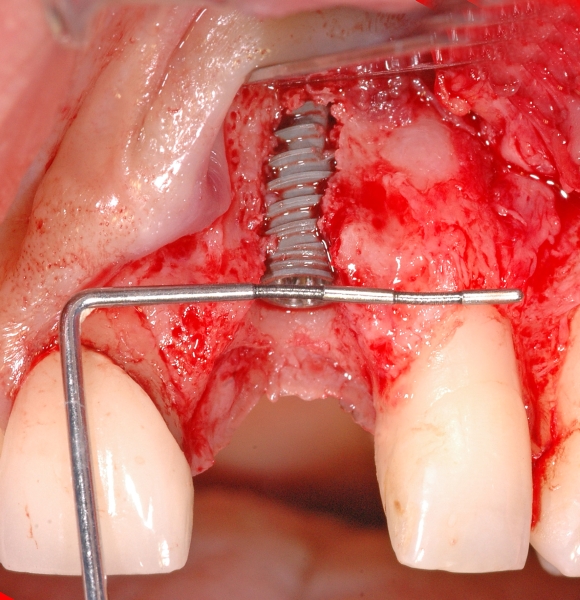

5/18 - Situation after implantation showing a buccal defectGBR together with soft tissue augmentation with mucoderm® and maxresorb® - Dr. S. Scherg